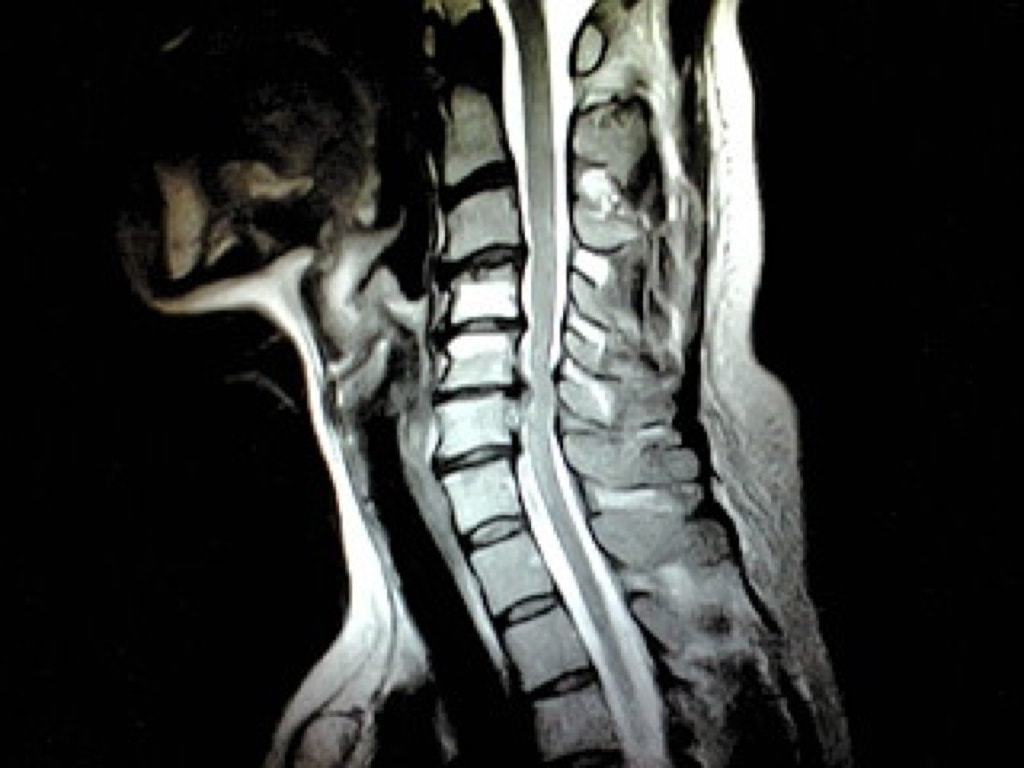

MRIドックのご案内

当クリニックでは脳神経外科領域の診療の他にMRIを用いた様々な検診メニューをご用意いたしました。『病状はなく病院へ行くほどではないけれど何か気になる』『ご自身の体の状態を正確に知りたい』などの場合にお役に立てる事と存じます。

病気の早期発見のために、最新のMRIを用いた本格的な検診。

大病院などで用いられている最新のMRIを使用し、精度の高い結果を得、かつ痛みや不快感を極力排除することを可能にしました。

検査画像は、豊富な経験を持つ専門性の高い読影医が担当し、読みやすく質の高いレポートとしてご提供します。また、ご要望に応じて、医師の説明を受けながら、自分の目で検査の画像を確認し、現在の健康の状態を理解して頂くことも出来ます。